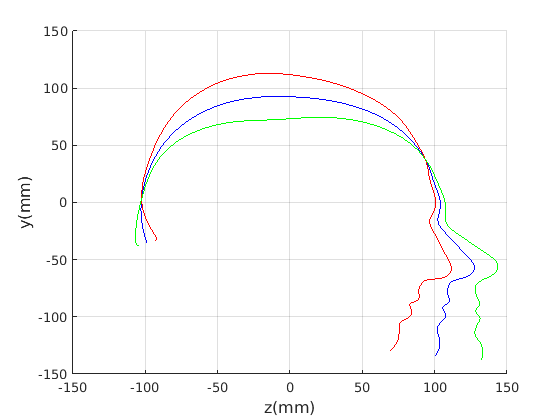

Figure 16 shows examples of the robust ellipse fit for four head profiles. The centre of the ellipse is used in a pose normalisation procedure where the ellipse centre is used as the origin of the profile and the angle from the ellipse centre to the nasion is fixed at -10 degrees. We call this Ellipse Centre - Nasion (ECN) pose normalisation and later compare this to GPA. The major and minor axes of the extracted ellipses are plotted as red and green lines respectively in Fig. 16.

|

Figure 17 shows all 100 profiles overlaid with the same alignment scheme. The median value of major ellipse axis and the ellipse centre-nasion angle differ by 3.6 degrees, so that when the nasion angle is fixed at -10 degrees, the median ellipse angle is -6.4 degrees (cf. -7.4 degrees with manual landmarking of the nasion). We noted regularity in the orientation of the fitted ellipse as is indicated by the clustering of the major (red) and minor (green) axes in Fig. 17 and the histogram of ellipse orientations in Fig. 18. For most people, the major axis of the ellipse is closely aligned with the y-axis (upright), and titled slightly forwards. A minority of heads (9%) in the training sample have their major ellipse axes closer to the vertical (these relatively tall and short heads are known as brachycephalic.) Ellipse axis clustering (relative to the fixed ellipse centre-nasion line) does not appear to be sharply defined. This is because many crania are close to circular in cross-section, making the orientation of these angles sensitive to small changes in shape from one person to the next. Note also the variation at the back of the head due to a variety of hair styles, some of which protrude from under the cap. We limit the region over which we model the cranial shape in order to crop this unwanted data out.